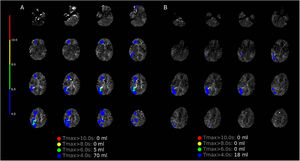

More infoMujer de 42 años que desarrolla hemorragia subaracnoidea (Hunt y HessV, FisherIII) secundaria a un aneurisma sacular en el segmento C6 derecho. Se realizó tratamiento endovascular con coils, pero presenta vasoespasmo difuso, comenzando tratamiento médico. Doppler transcraneano con vasoespasmo persistente, inicia milrinona y posterior angioplastia de vasos intracraneales, con resultados parciales. Se evidencia isquemia cerebral retardada refractaria en tomografía de perfusión (fig. 1A), se realizó bloqueo del ganglio estrellado con bupivacaína y lidocaína. El Doppler transcraneal posterior reveló una mejoría del vasoespasmo, confirmándose en tomografía de perfusión (fig. 1B). Este caso subraya los desafíos en el manejo del vasoespasmo cerebral refractario y destaca el papel potencial del bloqueo del ganglio estrellado como terapia de rescate.